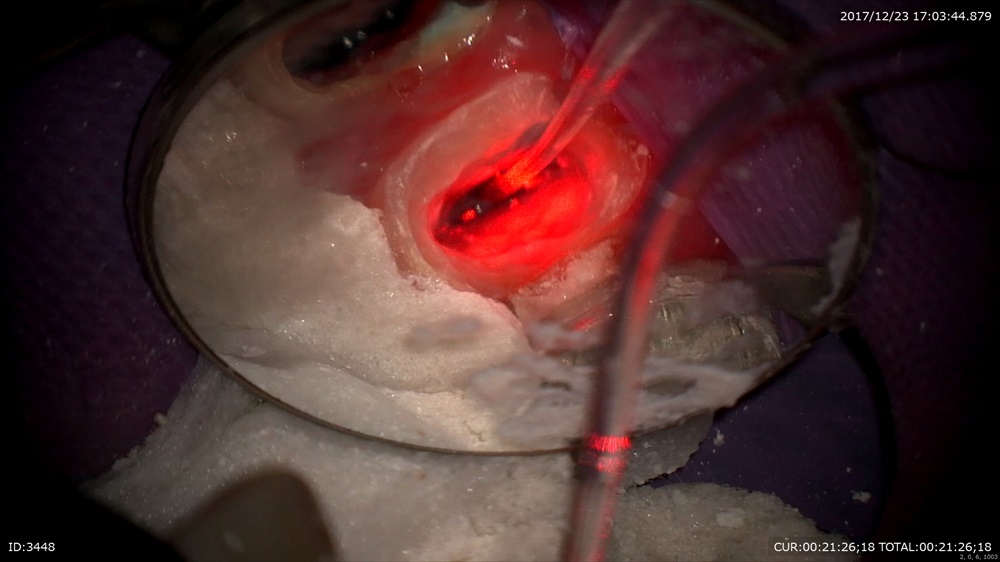

最後の患者さまも精密根管治療で歯の保存。今日は3回目。最後の感染源(汚れ)にアタック!

マイクロエキスカで

そーっと

そして根管充填